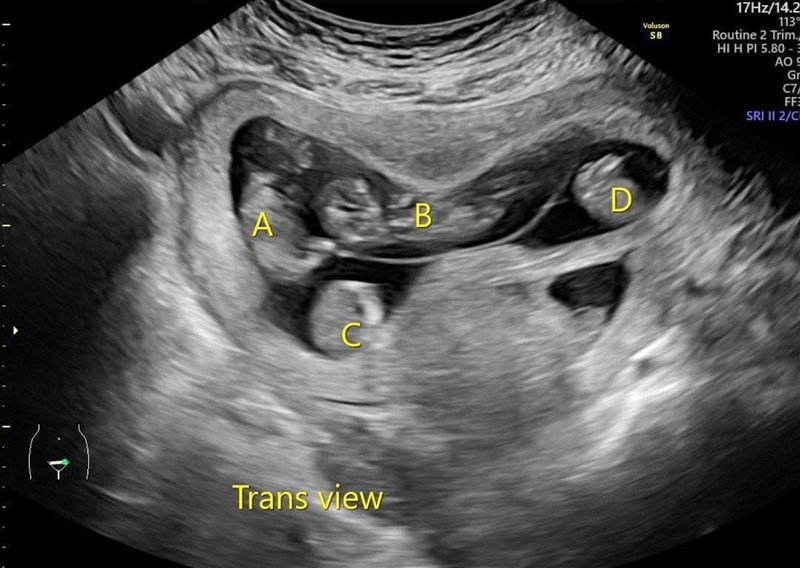

郭小姐接受RFA減胎手術前的同卵四胞胎(A、B、C、D)超音波影像。圖/蕭勝文醫師提供

【記者陳玲芳台北報導】34歲郭小姐,經歷三次試管嬰兒療程,終於盼到成功懷孕,不料竟是同卵四胞胎與一個單胎。考量多胞胎的高風險,夫妻在多家婦產科診所詢問「減胎手術」,得到的選項都是「全留」或「全流」,直到台北長庚利用「射頻燒灼減胎技術」,將她減為同卵三胞胎,去年郭小姐才在31周時,接受剖腹產手術,順利產下三名健康女嬰。

第七周時,郭小姐的單胎自行停止生長,胚胎萎縮,她和先生著急走遍婦產科診所與醫院詢問同卵四胞胎「減胎手術」,得到的選項卻是「全留」或「全流」,而且全留不一定都能順利生下來,因為使用氯化鉀的減胎手術,會影響同一胎盤的所有胎兒。

直到找台北長庚醫院蕭勝文醫師諮詢「射頻燒灼減胎技術」,一切才有了轉機。由於四胞胎發生早產與母體併發症的風險太高,因此決定在第15周接受射頻減胎手術後,減為同卵三胞胎。

台北長庚醫院婦產科系主任洪泰和指出,台北長庚從2020年開始執行這項技術,至今已完成超過25例RFA射頻燒灼手術,成功率超過九成;文獻上僅有同卵四胞胎減胎為雙胞胎,尚未報導過成功減為同卵三胞胎且順利生產的案例。